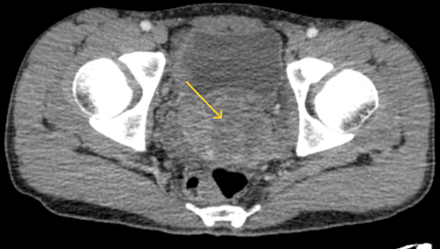

- Chụp CT ổ bụng không tiêm thuốc: Tiểu khung lệch trái có khối tỷ trọng tổ chức ~30HU kích thước mm 74x43x43mm, xung quanh có vài hạch kích thước lớn nhất 18x12mm. Gan kích thước bình thường, bờ đều. Nhu mô hạ phân thùy trước, sau và gan tái có các khối giảm tỷ trọng kích thước lần lượt 62x48mm, 40x34mm, 27x23mm, bờ đều rõ.

Hình 2: Hình ảnh chụp CT ổ bụng có khối vùng tiểu khung lệch trái chèn ép gây giãn đài bê thận - niệu quản trái (mũi tên vàng)